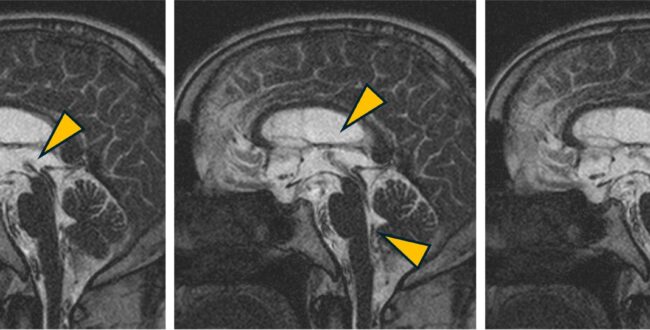

PSIF sequenceを用いたflowの観察